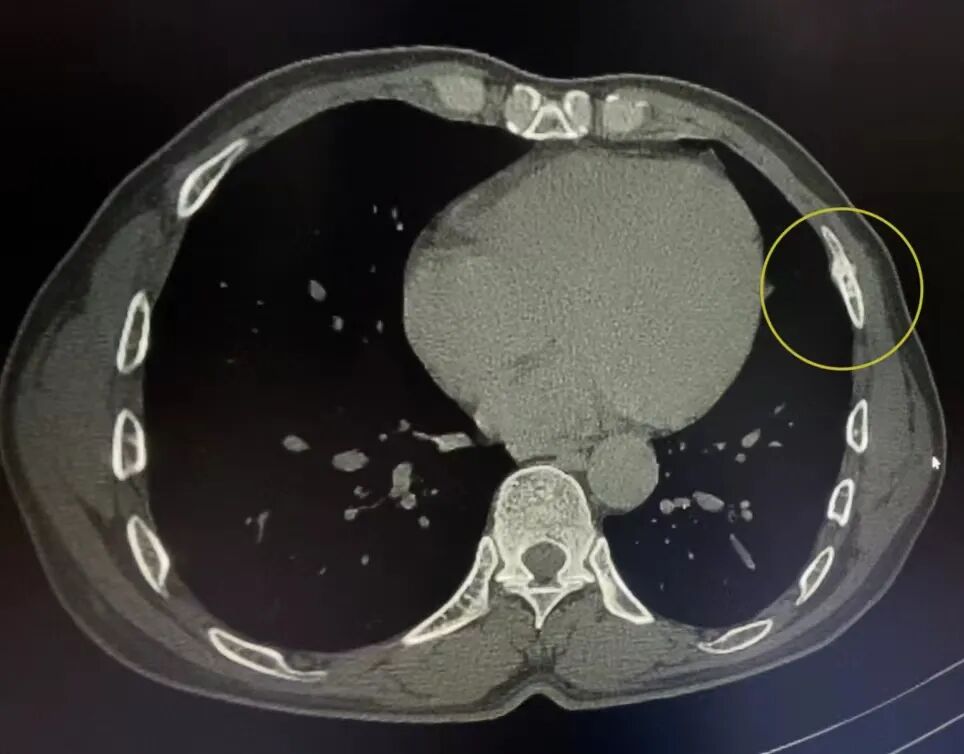

案例2、30岁患者被撞后到院检查,平片显示未见异常,CT扫描显示右侧第六肋骨不全性骨折。